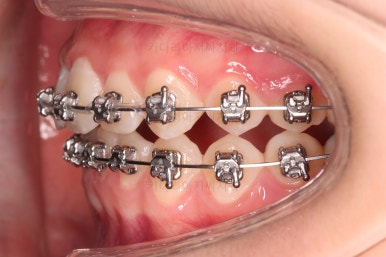

✅ 앵글씨 2급 부정교합

이번 환자분은 앵글씨 2급 부정교합이었는데요.

정상교합에 비해서 윗니가 상대적으로 앞에 아랫니가 상대적으로 뒤에 위치한 부정교합이 앵글씨 2급 부정교합입니다.

거꾸로 아랫니가 앞에 위치한 부정교합은 앵글씨 3급 부정교합입니다.

이번 환자분은 어금니가 위아래가 지그재그 서로 엇갈려 꽉 끼이는 교합이 아니라 1대1로 치아가 부딪혀 있는 상태였습니다.

이런 경우는 치아가 마모가 매우 잘되고 치아의 잇몸 근처 부분이 빨리 패여져 나가거나 잇몸 퇴축도 빨리 오게 됩니다. 물론 씹는 기능도 떨어지게 마련이고요.